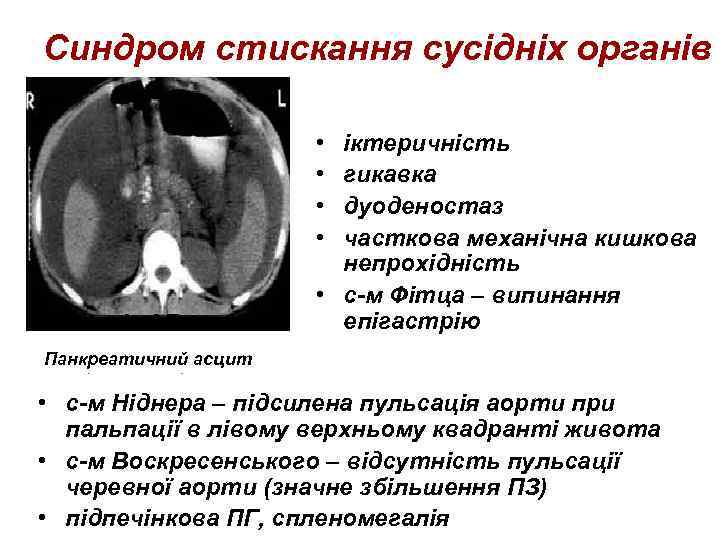

Синдром стискання сусідніх органів • • іктеричність гикавка дуоденостаз часткова механічна кишкова непрохідність • с-м Фітца – випинання епігастрію Панкреатичний асцит • с-м Ніднера – підсилена пульсація аорти при пальпації в лівому верхньому квадранті живота • с-м Воскресенського – відсутність пульсації черевної аорти (значне збільшення ПЗ) • підпечінкова ПГ, спленомегалія

Синдром стискання сусідніх органів • • іктеричність гикавка дуоденостаз часткова механічна кишкова непрохідність • с-м Фітца – випинання епігастрію Панкреатичний асцит • с-м Ніднера – підсилена пульсація аорти при пальпації в лівому верхньому квадранті живота • с-м Воскресенського – відсутність пульсації черевної аорти (значне збільшення ПЗ) • підпечінкова ПГ, спленомегалія